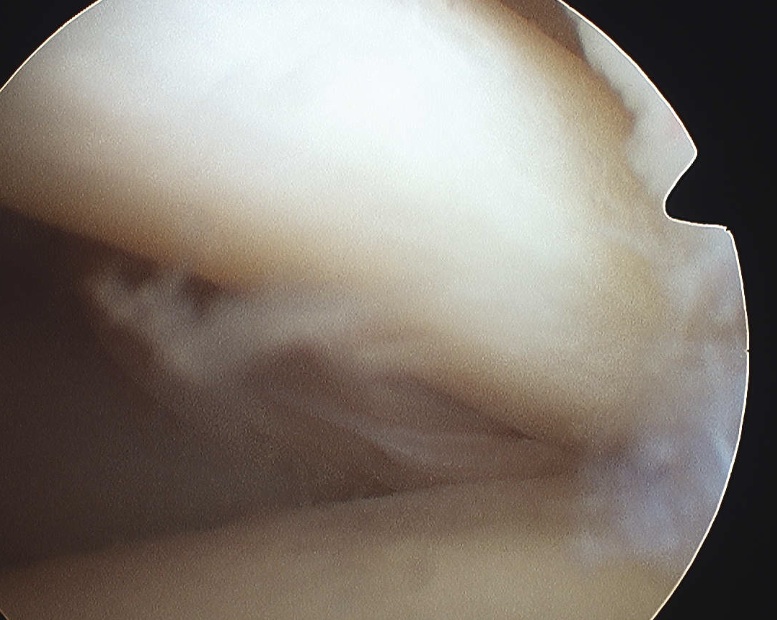

Rotator Interval - triangle of glenoid medial, biceps superior, subscapularis inferior

Humeral head cartilage

Glenoid cartilage

Labrum - anterior / inferior / posterior

Biceps tendon / insertion

Subscapularis

Glenohumeral ligaments